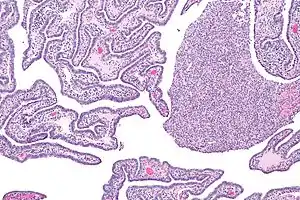

| Micrograph of acute and chronic salpingitis. H&E stain. | |